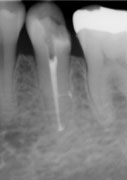

そこで根の形態が複雑だと判断した場合にはCT撮影を行い根の形態を3次元的に把握して治療を行っています(図2)。

図2